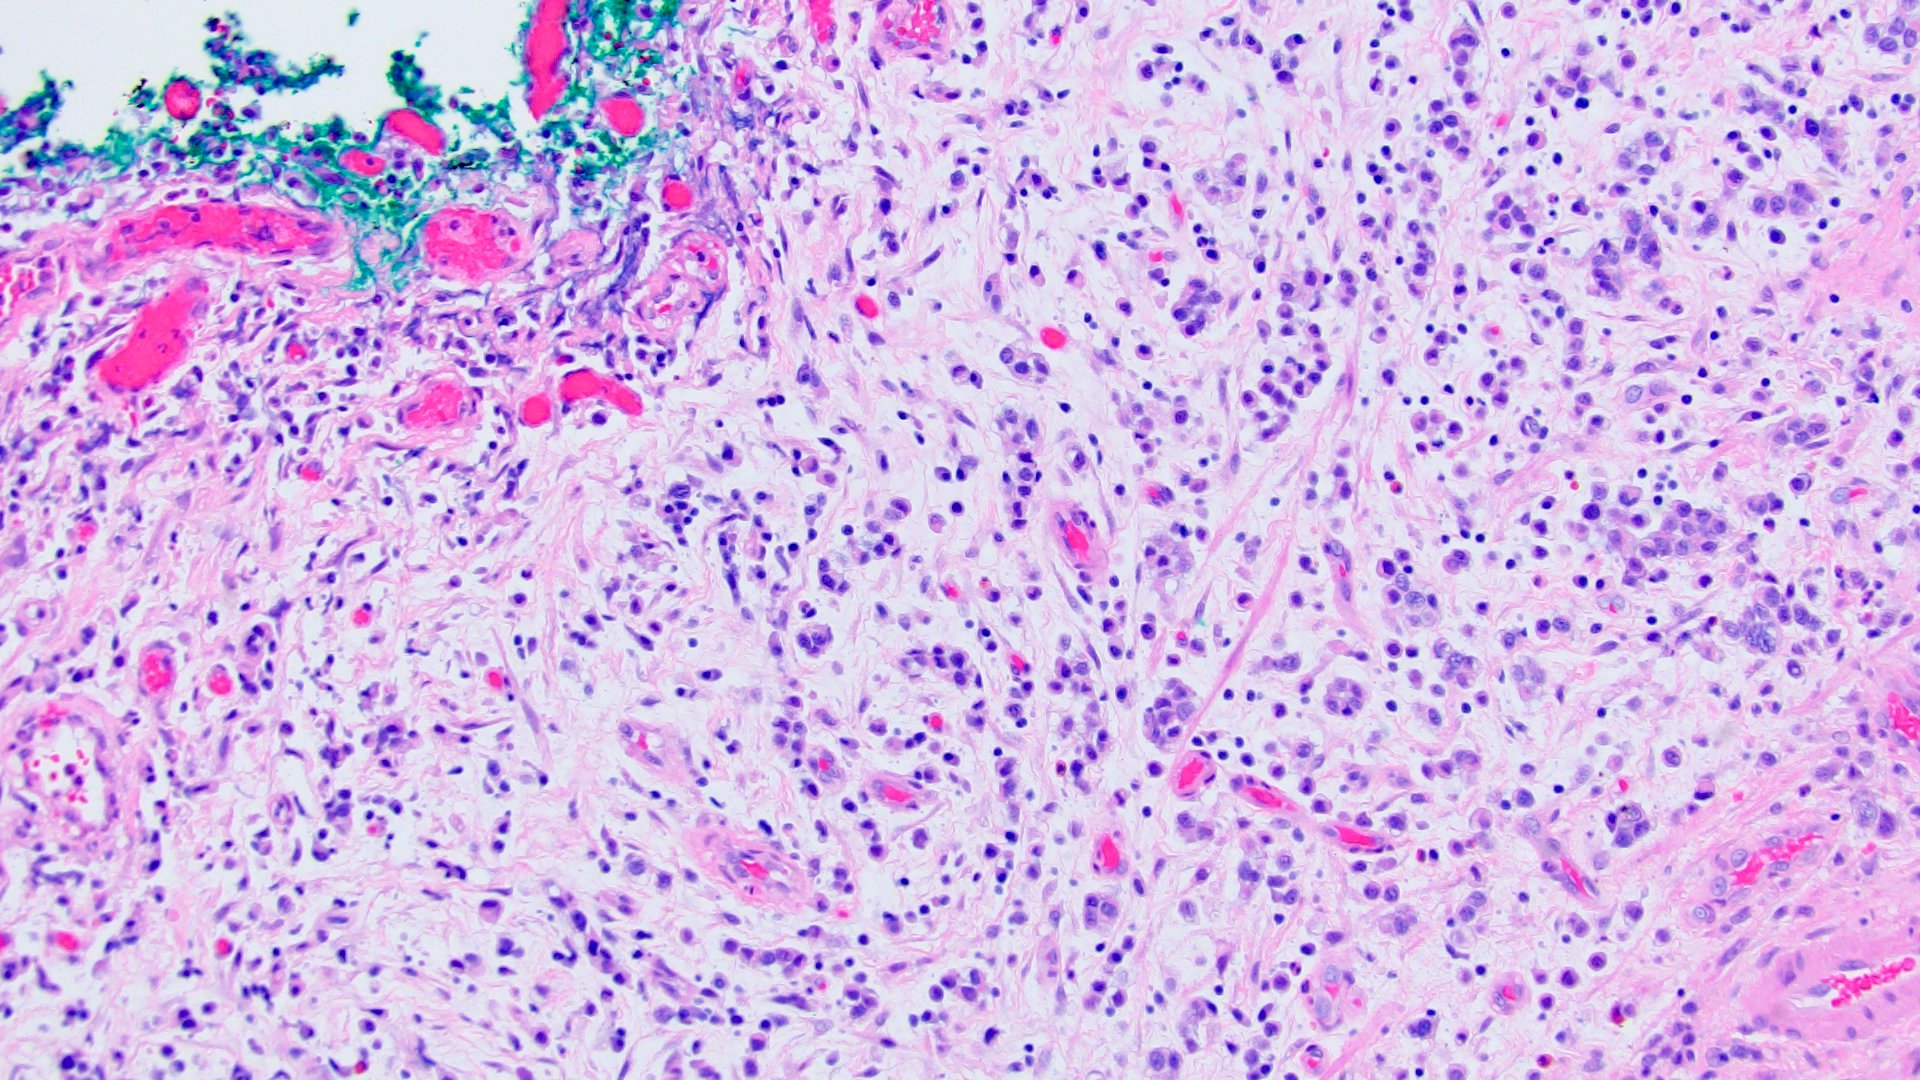

Microscopic (histologic) description

- Discohesive single cells with eccentrically placed nuclei and abundant eosinophilic cytoplasm

- Often deeply infiltrative but with minimal stromal reaction (Eur Urol Focus 2020;6:653)

- Further subclassified into classic, pleomorphic and desmoplastic subtypes:

- Classic: signet ring-like morphology, singly scattered and discohesive in loose aggregates forming cords (Hum Pathol 2019;90:27)

- Pleomorphic: similar to classic but with pleomorphic nuclei and more atypia; can be rhabdoid and bizarre appearing (Hum Pathol 2019;90:27)

- Desmoplastic: plasmacytoid neoplastic cells with a surrounding desmoplastic stromal response (Hum Pathol 2019;90:27)

- Associated with sarcomatoid variant in 31% of cases (Hum Pathol 2019;90:27)

- Often mixed with other histologic subtypes; in 1 case series, 53% of PUC had mixed histologic subtypes (Am J Clin Pathol 2017;147:500)

- Despite resemblance to signet ring carcinoma cells, notably lack extracellular mucin, contrasting to signet ring adenocarcinoma (Acta Cytol 1991;35:277, Am J Surg Pathol 1991;15:569)

Microscopic (histologic) images

Contributed by Timothy Isaac Miller, M.D., M.A., Nicole K. Andeen, M.D. and Maria Tretiakova, M.D., Ph.D.

Contributed by Lisa Han, M.D. and Ricardo Lastra, M.D. (Case #510)